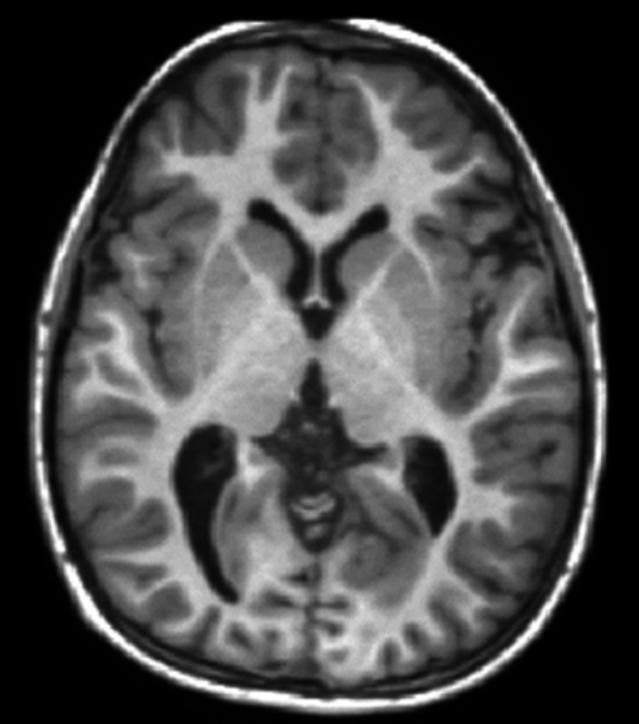

基于脑内不同结构T1弛豫时间的不同,核磁共振可以给出T1加权图像(T1 weighted image)。T1加权图像可以很好的区分大脑的灰质(神经元胞体聚集地)和白质(神经纤维聚集地),常用于大脑解剖结构成像。

T1加权图像可以很好区分大脑灰质和白质